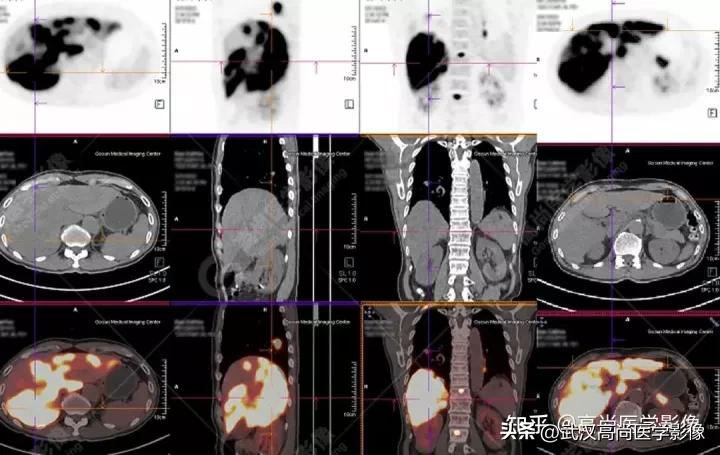

肝内多发片块状、团状FDG高摄取,SUVmax18.0,CT示弥漫低密度影,CT值约35Hu,边界欠清。

双侧锁骨区、左侧内乳区、双侧肺门、纵隔(1R、2、3A、4R、5、6、7、8、9组)、心底部、胰胃间隙多发淋巴结肿大,FDG高摄取,SUVmax16.3。

全身多处骨质成骨性破坏,FDG高摄取,SUVmax16.3。

左侧小脑半球两处等密度结节,FDG高代谢,SUVmax12.2。

灶周无水肿,普通CT平扫确实难发现病灶,PET通过代谢增高发现。

右肺下叶背段见一实性结节,大小约2.0cm×1.6cm×1.8cm,CT值33Hu,FDG高摄取,SUVmax13.0。

恶性CT征象:

病灶边缘分叶、短毛刺,其近端亚段支气管截断,瘤肺界面清楚,病灶远端片絮状阻塞性炎症。

右肺下叶背段周围型肺癌,伴多发淋巴结、左侧小脑半球、肝脏、骨多发转移。